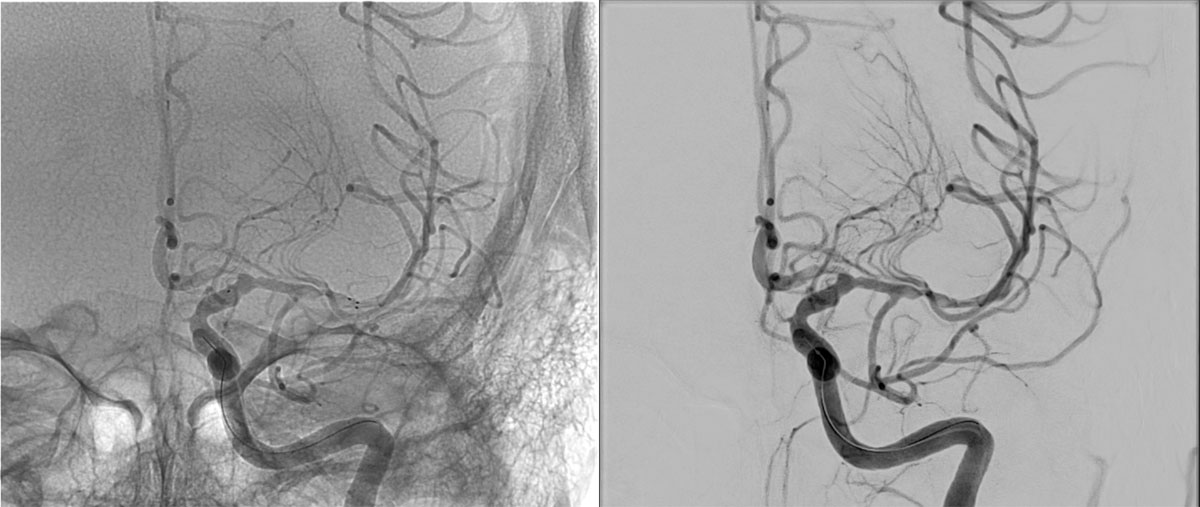

DSA

L - VERT

L - ICA